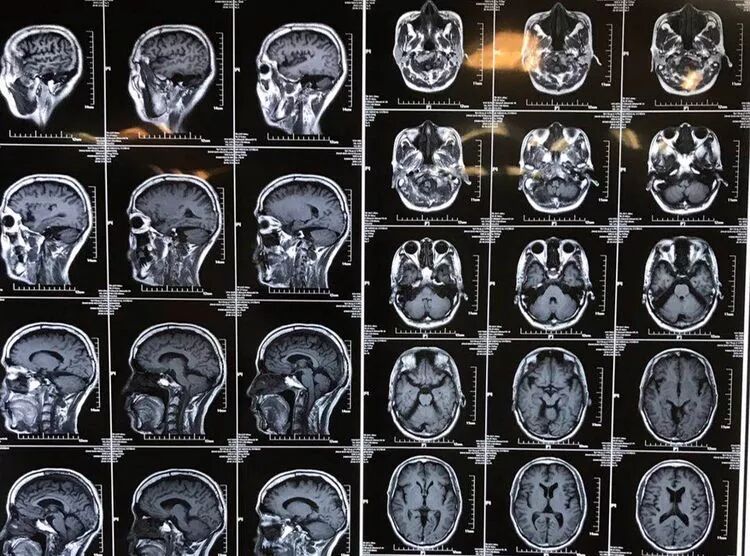

男性,59岁,半年前无诱因出现右半身麻木,伴右侧肢体乏力,右胸壁多汗,行走后右下肢抽痛明显,于当地医院就诊,查颈椎+胸椎+腰椎MRI示“颈髓脊髓空洞,腰4-5椎间盘突出”,对症治疗后症状无明显缓解。现为求进一步诊治,来西安交通大学第一附属医院,门诊以“脊髓空洞”收住入院。

入院查体:双侧瞳孔等大等圆,直径3.5mm,直接对光反射双侧灵敏,间接对光反射双侧灵敏。右颞顶枕部皮肤浅感觉减退,右侧躯体及右侧肢体皮肤浅感觉减退。左侧肢体肌力5级。右侧肢体肌力4级。右侧踝阵挛阳性。双侧Babinski征(+)。

影像学资料

诊断:

1. Chiairi畸形并颈髓空洞

2. 脊柱侧弯

3. 腰4-5椎间盘突出